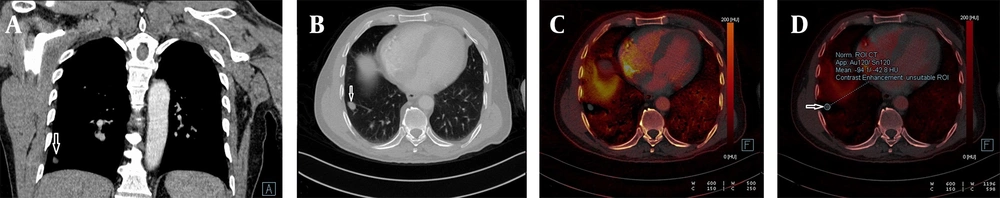

Each nodule was evaluated by a radiologist with 14 years of experience in thoracic imaging who was blinded to the histopathological results and previous radiologic features of the patients. To minimize bias in image analysis, a second radiologist was consulted in cases of disagreement, and if necessary, a third experienced radiologist provided the final decision. The first evaluation involved a qualitative visual assessment, in which a VNC image of the iodine component in translucent mode was displayed as a background color overlay. The manufacturer-defined iodine retention value was set at higher than 50% for default color-coding. The presence of any color (orange or red) in the nodule was considered indicative of contrast enhancement, while a black color (no color-coding) was interpreted as the absence of contrast enhancement. The results were recorded in a binary format as "present" (orange-red) or "absent" (black) (Figures 1 and 2).

A, The weighted average image; B, The virtual non-enhanced image; C, The iodine-enhanced image; and D, The image of the iodine load are observed in dual-energy computed tomography, DECT. C - D, The iodine component is shown as a color overlay on a background virtual non-enhanced image in translucent mode.

Detection of calcification in a lung nodule on a virtual non-contrast-enhanced image in dual-energy computed tomography, DECT. A, The weighted average image of the lesion in the apical segment of the left lung; B, The virtual non-contrast-enhanced image showing a small calcification around the nodule (white arrow); C, Dual view; and D, Iodine load are shown; E, No significant 18-FDG uptake was observed in the PET-CT images obtained from the same patient.